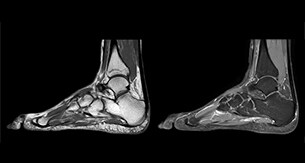

“При визуализации периферических суставов режим mDIXON TSE помогает диагностировать травмы связок или сухожилий, дегенеративные и воспалительные патологии, такие как остеоартрит и ревматологические заболевания, а также злокачественные новообразования.” “При оценке сухожилий и связок вокруг колена, голени, таза и локтя режим mDIXON TSE обусловливает достоверность диагностики благодаря способности получения изображений с подавлением и без подавления сигнала жира без дополнительных затрат времени. Это стало возможным в связи с тем, что сканирование в 2-точечном режиме mDIXON выполняется быстрее, чем с помощью обычного 3-точечного метода Dixon. Он может обладать более высокой эффективностью, поскольку помогает избежать увеличения продолжительности сканирования.” “mDIXON TSE sequences allow simultaneous characterization of morphological changes from the in-phase T2-weighted images and visualization of edematous changes, thanks to the water T2-weighted images from the same acquisition. Anatomical and morphological considerations could be a partial or complete ligament tear, a bony avulsion or hematoma.” “For soft tissue assessment mDIXON brings similar benefits. For example in one T2-weighted mDIXON TSE acquisition, having the multiple contrasts helps us assess abnormalities in peripheral nerves fascicles, which may be due to anatomical or inflammatory changes..” “In peripheral joints, we get good image quality in difficult areas with mDIXON TSE. Fat suppressed images appear homogeneous over the entire image, even with large coverage at 3.0T – for instance in scapular or hip girdles – or in the bearing areas or around metal prostheses*, where fat suppression is often deficient with STIR or spectral fat suppression, causing diagnostic difficulties. If a diagnostic image is right the first time, we don’t need to repeat or add a sequence.” “mDIXON TSE sequences allow simultaneous characterization of morphological changes from the in-phase T2-weighted images and visualization of edematous changes, thanks to the water T2-weighted images from the same acquisition. Anatomical and morphological considerations could be a partial or complete ligament tear, a bony avulsion or hematoma.” “For soft tissue assessment mDIXON brings similar benefits. For example in one T2-weighted mDIXON TSE acquisition, having the multiple contrasts helps us assess abnormalities in peripheral nerves fascicles, which may be due to anatomical or inflammatory changes..”

“С помощью режима mDIXON TSE мы получаем изображения периферических суставов хорошего качества, даже на сложных участках.

Сигнал от жира подавляется однородно по всему изображению, даже в исследованиях с большим охватом при 3,0 Тл, например в исследованиях лопаток, тазового пояса, опорных поверхностей или тканей вокруг металлических протезов*, где технология STIR или функция спектрального подавления жира не обеспечивают необходимого уровня подавления. Если удается с первого раза получить нужное диагностическое изображение, нам не придется повторять сканирование или добавлять последовательность.” “Последовательности mDIXON TSE позволяют одновременно диагностировать анатомические изменения по синфазным T2-взвешенным изображениям и визуализировать отечные изменения благодаря T2-взвешенным изображениям воды, полученным в ходе того же сканирования. Возможные анатомические заключения: частичный или полный разрыв связки, авульсия кости или гематомa.” “При оценке мягких тканей режим mDIXON дает аналогичные преимущества. Например, всего одно сканирование с T2-взвешенной последовательностью mDIXON TSE, позволяющей получить несколько типов контраста, помогает оценить аномалии пучков периферических нервов, которые могут быть обусловлены анатомическими изменениями или воспалением.” “mDIXON TSE sequences allow simultaneous characterization of morphological changes from the in-phase T2-weighted images and visualization of edematous changes, thanks to the water T2-weighted images from the same acquisition. Anatomical and morphological considerations could be a partial or complete ligament tear, a bony avulsion or hematoma.” “For soft tissue assessment mDIXON brings similar benefits. For example in one T2-weighted mDIXON TSE acquisition, having the multiple contrasts helps us assess abnormalities in peripheral nerves fascicles, which may be due to anatomical or inflammatory changes..” “In peripheral joints, we get good image quality in difficult areas with mDIXON TSE. Fat suppressed images appear homogeneous over the entire image, even with large coverage at 3.0T – for instance in scapular or hip girdles – or in the bearing areas or around metal prostheses*, where fat suppression is often deficient with STIR or spectral fat suppression, causing diagnostic difficulties. If a diagnostic image is right the first time, we don’t need to repeat or add a sequence.” “mDIXON TSE sequences allow simultaneous characterization of morphological changes from the in-phase T2-weighted images and visualization of edematous changes, thanks to the water T2-weighted images from the same acquisition. Anatomical and morphological considerations could be a partial or complete ligament tear, a bony avulsion or hematoma.” “For soft tissue assessment mDIXON brings similar benefits. For example in one T2-weighted mDIXON TSE acquisition, having the multiple contrasts helps us assess abnormalities in peripheral nerves fascicles, which may be due to anatomical or inflammatory changes..”